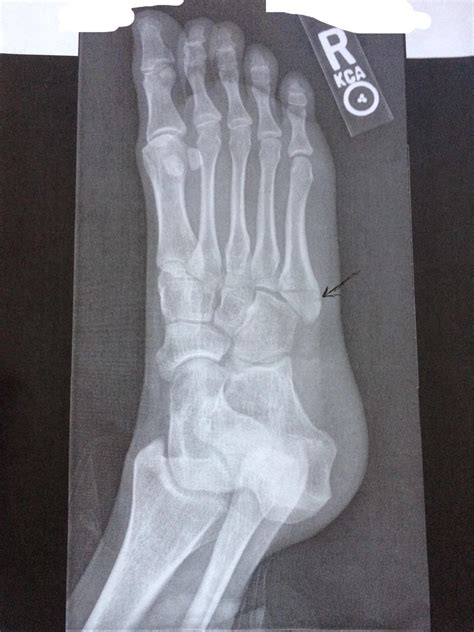

A Pseudo Jones Fracture is a specific type of fracture that occurs in the fifth metatarsal bone of the foot. This bone is located on the outer side of the foot and connects to the little toe. The term "Pseudo Jones" distinguishes it from a true Jones fracture, which occurs at the base of the fifth metatarsal. A Pseudo Jones Fracture typically involves a fracture at the proximal diaphysis of the fifth metatarsal, just distal to the tuberosity.

• Order X-rays to visualize the fracture and determine its location and severity.

Pseudo Jones Fracture Proximal diaphysis of the fifth metatarsal Sudden impact, twisting, or rolling the ankle Non-surgical (RICE, immobilization), Surgical (ORIF, bone grafting)

Jones Fracture Base of the fifth metatarsal Sudden impact, twisting, or rolling the ankle Non-surgical (RICE, immobilization), Surgical (ORIF, bone grafting)